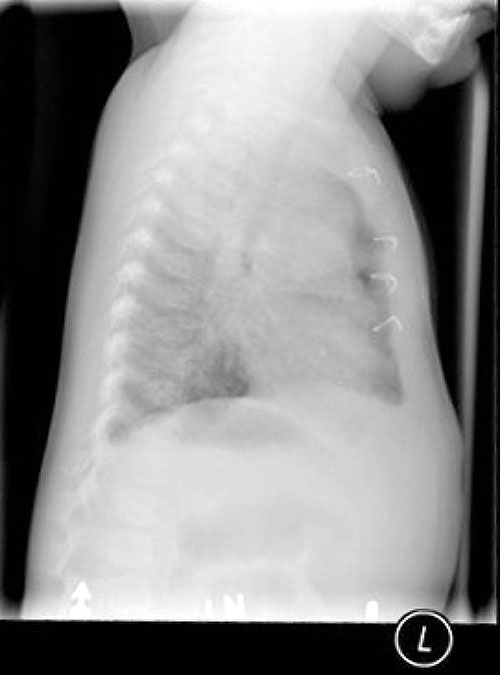

The

CHEST X-RAY is seen below.

Enlarge this CHEST

X-RAY (LEFT). Enlarge this CHEST

X-RAY (RIGHT)

WHAT IS YOUR INTERPRETATION?